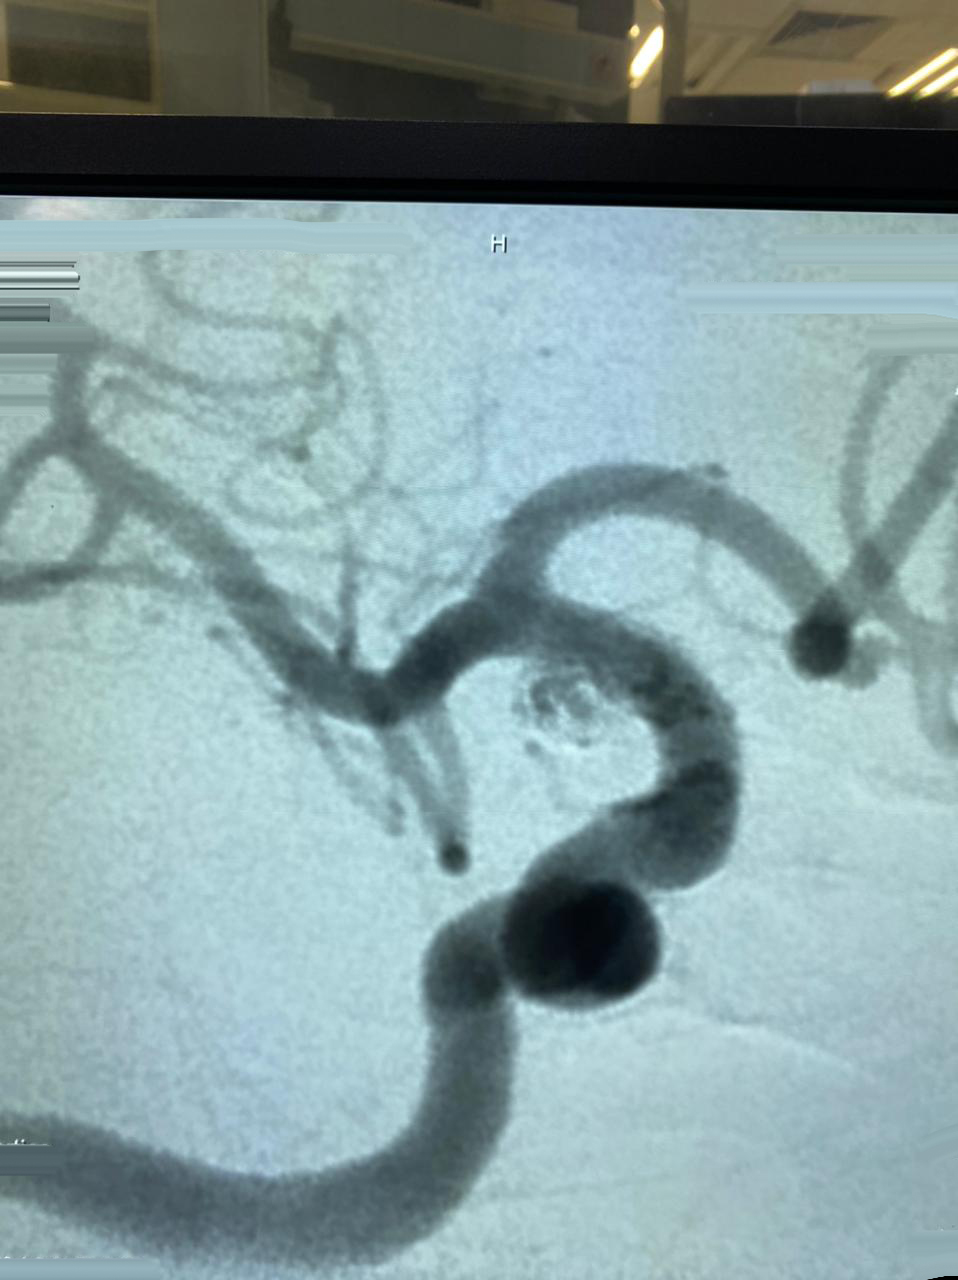

HCorBJ realiza procedimento de Embolização de Aneurisma Cerebral

O procedimento de Embolização de Aneurisma Cerebral é realizado no Setor de Hemodinâmica, sob anestesia geral, com um aparelho de imagem de última geração. O tratamento endovascular, é uma opção minimamente invasiva para as doenças cerebrovasculares.

“O primeiro caso de Embolização de Aneurisma Cerebral em Ponta Grossa, com stent diversor de fluxo, foi realizado no Hospital do Coração Bom Jesus em dezembro de 2018, o HCorBJ tem estrutura excelente para isso, tanto para realização do método, quanto no atendimento pós- operatório dos pacientes na Unidade de Terapia Intensiva (UTI) e enfermaria, com equipes altamente especializadas”, ressalta Sabatini.